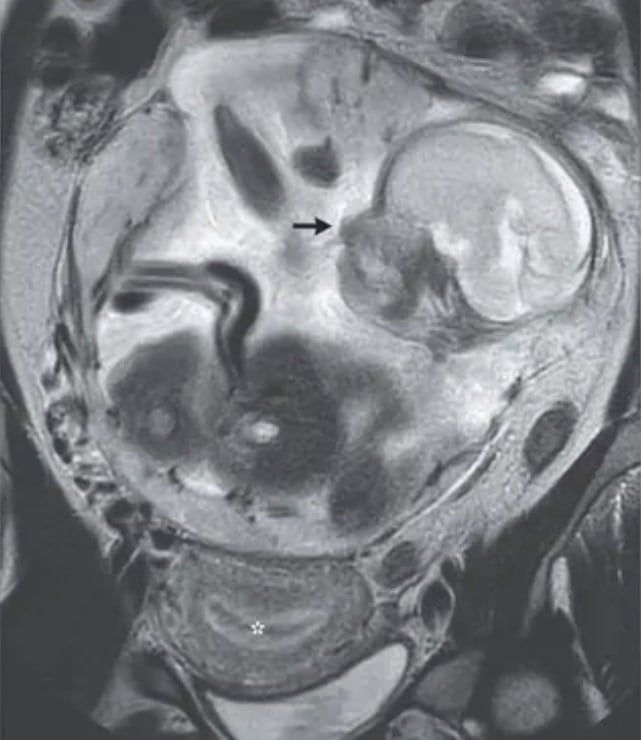

腹腔で発育していた胎児の画像(その下の星印で示されたのが子宮)

腹腔で発育していた胎児の画像(その下の星印で示されたのが子宮) / Credit: Guillaume Gorincour et al., The New England Journal of Medicine(2023)

おそらく、女性が訴えていた腹痛は、腹腔内で大きくなった胎児が周りの臓器を圧迫していたからだと考えられます。

胎児は羊水の入った羊膜に包まれており、へその緒もつながっていて、正常に発育しているようでした。

また通常は子宮内にできるはずの「胎盤」も胎児とともに腹腔にあり、女性の背骨の付け根近くの腹部内壁に付着していたようです。